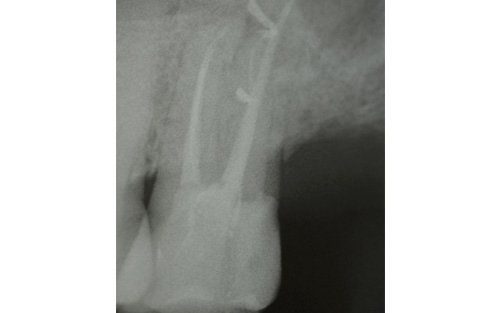

This treatment should be reserved for teeth that have irreversible pulp pathology (the nerve of the tooth) or an infection of the dental canals that has caused an abscess (acute apical periodontitis) or a granuloma (chronic apical periodontitis). While in the first two cases the tooth is very painful and the patient immediately seeks the dentist, the case of the chronic form is often silent, and therefore the patient may not notice anything for a medium to long period of time. In such conditions, it is only an X-ray image, taken during routine check-ups, that detects its presence. Root canal therapy can be completed by placing a latest-generation post inside the canal, as a means of retaining the material used for the reconstruction of the tooth. It will be up to the clinician to decide whether or not the restoration requires this additional anchoring system.